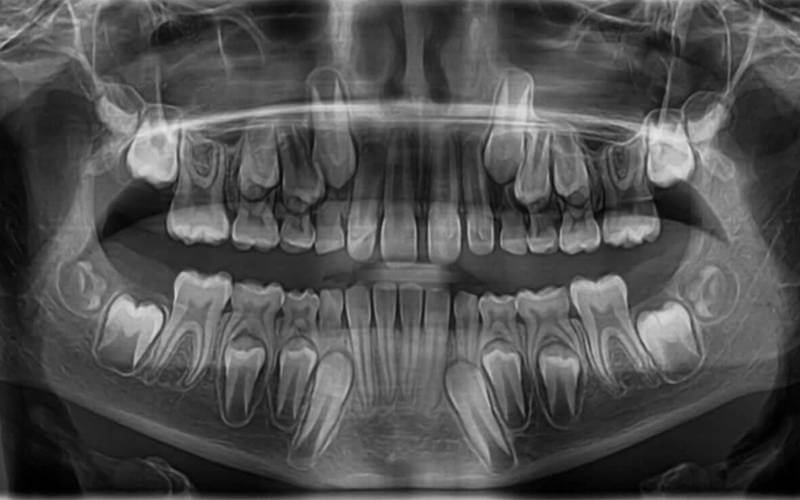

Panorámaröntgen képet nem szükséges minden fogászati kezelés előtt készíteni. Általában akkor javasoljuk pácienseinknek, ha a pontos diagnózishoz illetve a kezelés precíz megtervezéséhez átfogó képet kell kapjunk az állkapcsokról, a fogakról és a környező szájüregi struktúrákról.

A bölcsességfogak állapotának felmérésekor is alkalmazzuk, például annak megállapítására, hogy vannak-e elakadt fogak, azok közel vannak-e az idegekhez, illetve torlódást okoznak-e, vagy okozhatnak-e.

Panoráma röntgenfelvételre van szükségünk fogászati implantátum tervezéséhez, például az állkapocs csont állapotának, magasságának, vastagságának, valamint a sinus/idegek elhelyezkedésének feltérképezése értékelése miatt.

Panorámaröntgenre van szükség fogszabályozássalkapcsolatos beavatkozások esetében is, elsősorban az állkapocs növekedésének, valamint a fogak helyzetének és a hiányzó, illetve többlet fogak értékelése érdekében.

Egyéb éllkapocs problémák esetében is szükség lehet panoráma röntgenfelvételre, így a feltételezett törések, ciszták, daganatok vagy csontbetegségek diagnosztizálása/kizárása érdekében.

Gyakoran indokol panoráma röntgenfelvételt komplex fogászati probléma is, például kiterjedt fogszuvasodás, bizonyos ínybetegség, amelyek csontvesztést okoznak, vagy ha egyszerre több fogat kell eltávolítani a kezeléshez pl. fogászati implantációhoz stb.

Előfordulhat, hogy rutin jellegű ellenőrzéseknál is szükség van panoráma röntgenfelvételre, például gyermekek/serdülők/fiatal felnőttek állandó fogainak vagy a beékelődött fogak fejlődésének ellenőrzése miatt.

Panorámaröntgenre tehát akkor van szükség, amikor a fogorvosnak átfogó képet kell kapnia a fogak állapotáról illetve a fogak környezetéről (állkapcsokról, kapcsolódó struktúrákról). Panorámaröntgent főleg műtéti- és szájsebészeti beavatkozások, fogszabályozás, fogászati implantáció vagy más komplex fogászati kezelések indokolhatnak.